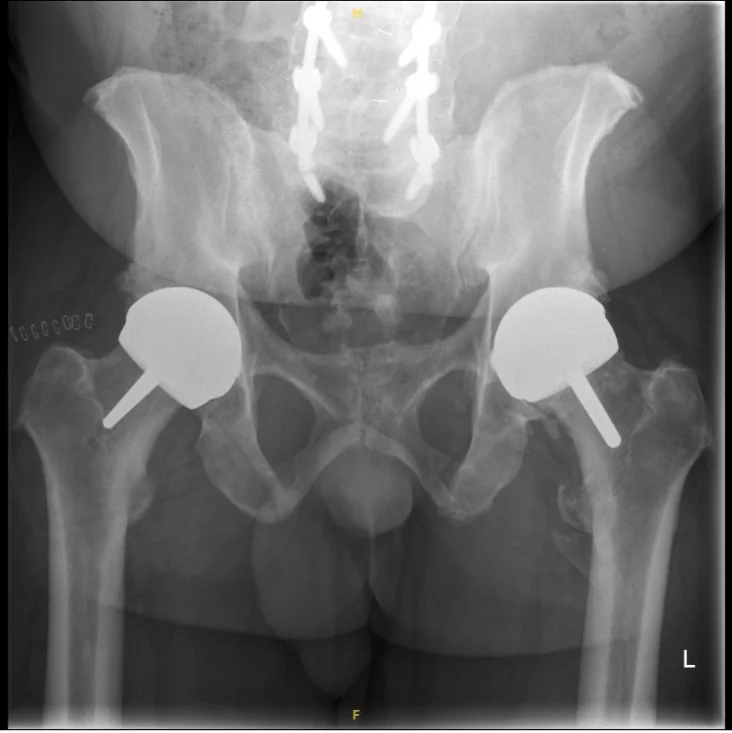

Surgical Images & X-rays

Hip resurfacing is a surgical procedure that treats hip arthritis while preserving significantly more of your natural bone than a traditional total hip replacement. Instead of removing the entire femoral head (the ball of the hip joint), it is reshaped and capped with a smooth metal or ceramic covering. The damaged hip socket is also resurfaced with a matching shell.

Mr Hussain selects the most appropriate implant for each patient based on their anatomy, bone quality, activity goals, and gender. He is one of few UK surgeons offering both metal-on-metal and ceramic-on-ceramic resurfacing options.

A ceramic-on-ceramic resurfacing implant suitable for both male and female patients. Eliminates metal ion concerns associated with traditional resurfacing. Uses hybrid fixation with cement in the femoral component.

The latest generation ceramic-on-ceramic resurfacing implant with totally cementless fixation. Suitable for both men and women. Represents the cutting edge of hip resurfacing technology.